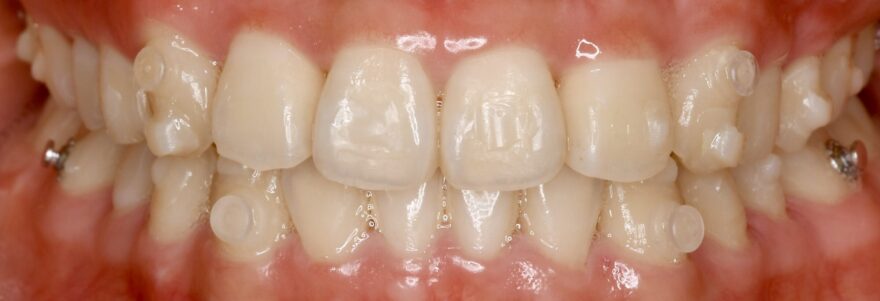

初診時の口腔内写真

上の八重歯が気になります。

八重歯の内側への移動量がとても多いことがわかります。